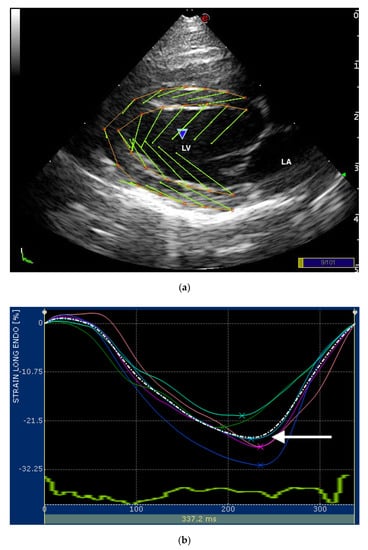

Images of the LV for STE were obtained from the RP4Ch and LAP4Ch views and three cineloops (at least three beats for each) from both echocardiographic views were acquired for off-line analysis. Both echocardiographic views were required for cats to be included in the analyses. The visualization of the LV was optimized obtaining the image with the longest long-axis dimension possible in both views. If necessary, we increased the sector width during the acquisition of the RP4Ch view. In this way, the foreshortening of the LV apex was avoided. All recorded cineloops were analyzed by one experienced examiner (D.C.) using the XstrainTM software (Esaote, Genova, Italy). A frame with an optimally visualized endocardial and epicardial borders were selected for both views. The software automatically traced 10 equidistant lines among 3 starting points fixed by the operator (2 at the mitral valve annulus and 1 at the LV apex) for delimiting both endocardial and epicardial borders. These 13 points followed the endocardial and epicardial border during entire cardiac cycle and the operator could check if tracking were optimal or the points needed to be manually adjusted (Figure 1). The software divided the LV into 6 segments and generated an average value of the longitudinal strain and strain rate. Only average value of the maximal systolic peak of the LV longitudinal strain and strain rate of the endocardial and epicardial border for both views were analyzed (Figure 1). The mean value of three consecutive cardiac cycles in sinus rhythm for each variable was obtained and used for statistical analysis.

Figure 1.

(a) Snapshot of 2-dimensional speckle tracking analysis from the right parasternal four-chamber view optimized for visualization of the left ventricle (LV) in a healthy cat. Thirteen points delimit and follow the endocardial and epicardial border of the LV, frame-by-frame during entire cardiac cycle. Green arrows represent the vectors of each point and their direction of displacement; (b,c) snapshots of (b) endocardial and (c) epicardial longitudinal strain curves of the LV. The software divided the LV into 6 segments (colored line) and generates an average value (dotted line). Only the systolic peak (white arrows) of the longitudinal endocardial and epicardial strain of the LV were used. LV—left ventricle; LA—left atrium.